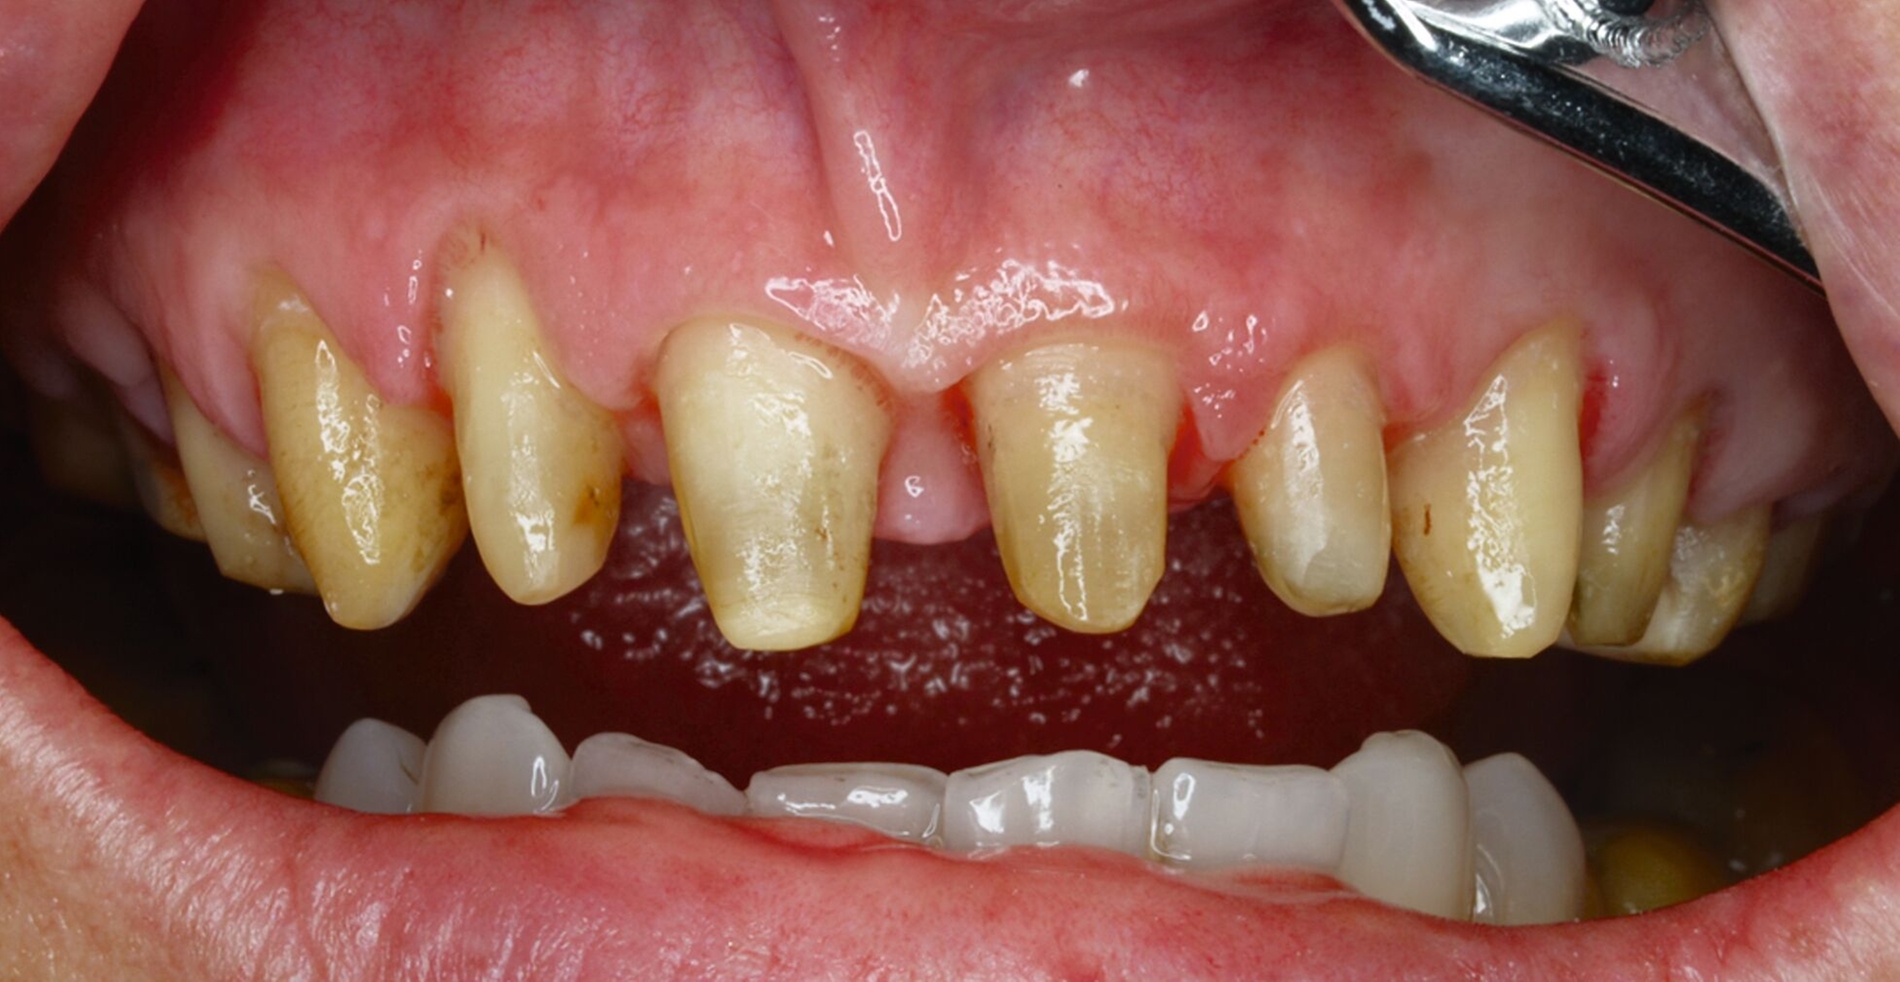

Klinisch zeigten sich diverse großflächig, mehrheitlich mit Amalgam gefüllte Seitenzähne, suffiziente endodontische Behandlungen an den Zähnen 16 und 14 sowie intakte Kronen an den Zähnen 16 und 48 (Abbildung 2). Ein Parodontaler Screening-Index (PSI) wurde erhoben (1-1-0-0-2-1), der stabile Verhältnisse nachwies. Das funktionelle CMD-Screening zeigte eine nicht-druckdolente Kaumuskulatur sowie eine uneingeschränkte Mundöffnung ohne Reiben und Knacken.

Tabelle 1 zeigt das entsprechende Befundschema mit den Taschentiefen mesial und distal, den Lockerungsgraden und den Sensibilitätsüberprüfungen mittels Kältespray (ViPr). Die Ruheschwebelage wurde mithilfe des Zielinsky-Zirkels auf 2 mm bestimmt. Die Nonokklusion im Seitenzahnbereich konnte auf circa 1,5 mm bemessen werden. Tabelle 2 spiegelt das entsprechende Okklusionsprotokoll wider. Das Okklusionsprofil wird auch in den Abbildungen 3a bis 3c deutlich.